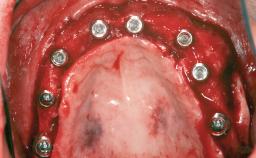

Replacement of Multiple Teeth in a Partially Dentate Posterior Mandible with a Fixed Dental Prosthesis Using a Flapless Approach

# of Teeth 4

# of Implants 4

Type of Implants One-Piece|Two-Piece